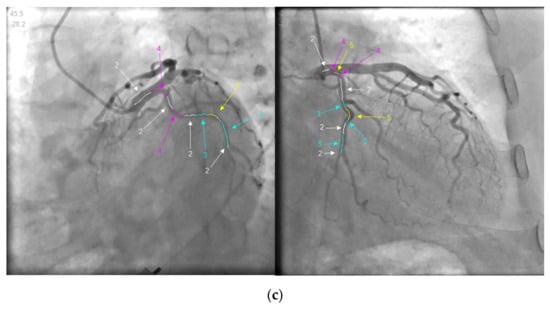

Our goal was to find out the vascular segments that are overlapping or distorted during projection in angiographic images. It is called OPE (overlapping or parallel elements) in this paper. As shown in Figure 3, several features of OPE can be summarized:

Figure 3.

The example of OPE. (a,b) are two sets of patient data. The red circle on the left image is where OPE is; the image on the right is the corresponding.

- The brightness of the pixel where OPE is located is often lower than the adjacent anterior and posterior pixels.

- OPE is often on the convex arc of the blood vessel.